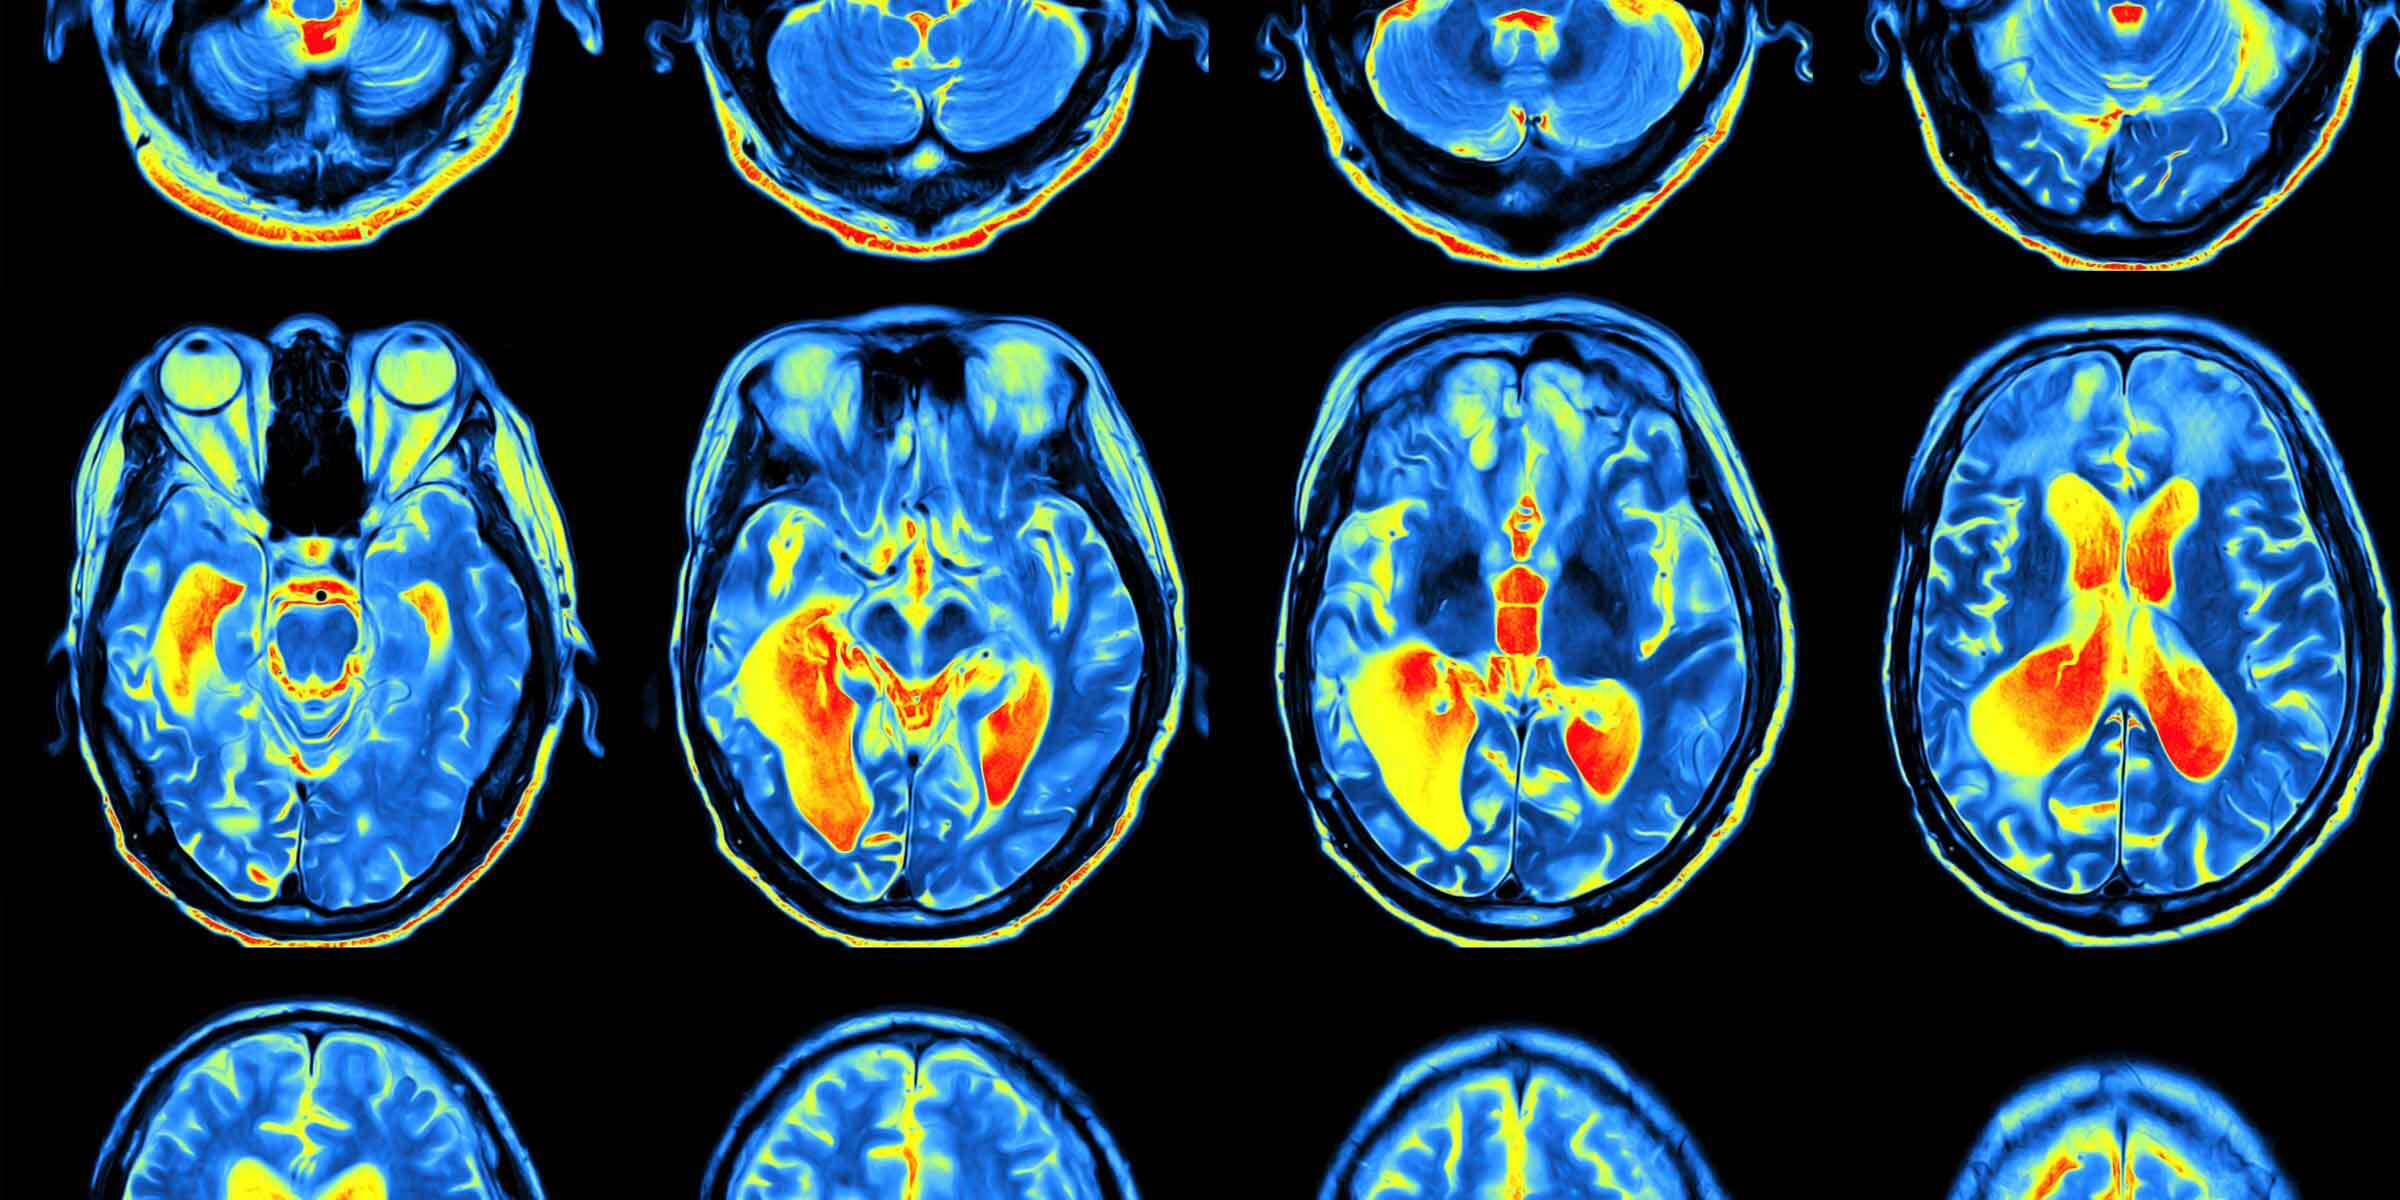

В ходе недавнего исследования, результаты которого опубликованы в журнале Neuron, учёные выявили участок мозга, генерирующий то, что они называют «сигналом реальности». Этот сигнал оценивается затем другой областью мозга, нарушение работы которого связывают с шизофренией.

Чтобы понять, как мозг отличает реальность от вымысла, учёные показывали участникам эксперимента трудноразличимые узоры и одновременно проводили сканирование их мозга. Люди смотрели на экран со статическим фоном, на котором иногда был наложен едва заметный узор из диагональных полос. Эти полосы могли быть наклонены как вправо, так и влево.

Далее участников попросили представить себе узор с левым или правым наклоном, глядя на экран, а затем указать, отображался ли один из узоров на самом деле. Когда они искали и представляли этот узор, они чаще говорили, что видели его, даже если его не было. Это значит, что они ошибочно принимали воображаемое за реальность. Также их мысленные образы были ярче, когда узор присутствовал, при условии, что он соответствовал тому, что они представляли. Получается, что и наше восприятие чего-то может влиять на воображение.

При помощи функциональной магнитно-резонансной томографии (фМРТ) мозга была выявлена более активная область, когда участники сообщали, что видели какой-то рисунок. Эта веретенообразная извилина находится в районе висков. Она активируется как при виде чего-то в реальности, так и при представлении этого. Интересно, что эта активация предсказывает, считаем ли мы что-либо реальным. Далее этот сигнал оценивается передней островковой долей. Активность выше определённого порога воспринимается как реальная, а активность ниже — как воображаемая.